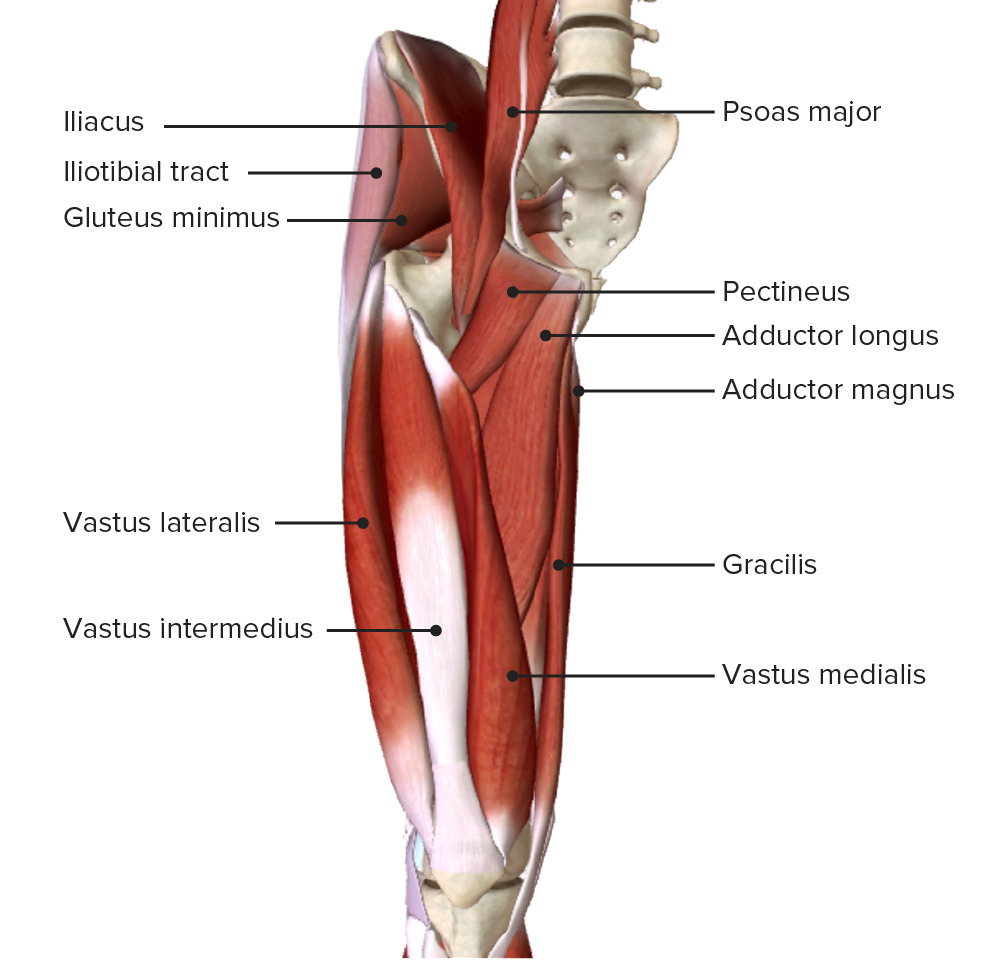

Анатомия и Функции Мышцы Adductor Magnus